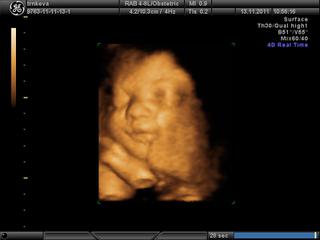

tak babule dnes nám 4D vyšlo na 100% a meno už máme dávno vybraté NINA